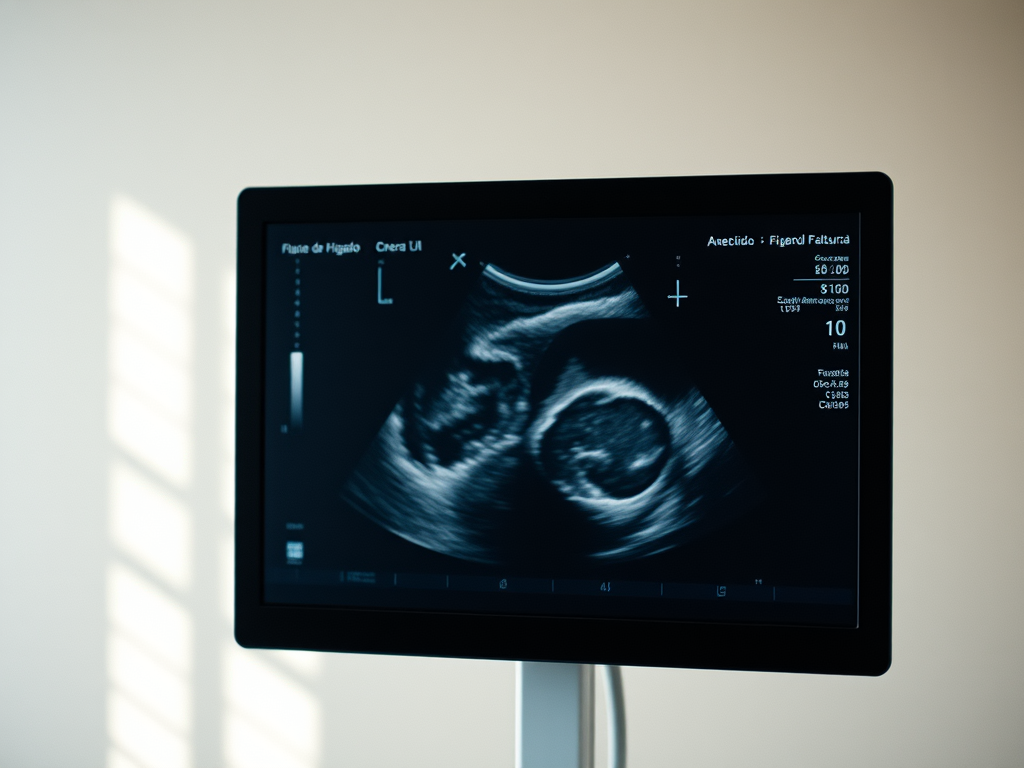

Los estudios de imagen son esenciales para el diagnóstico. La ecografía es la prueba inicial más útil, ya que normalmente puede diferenciar un quiste simple de otras lesiones quísticas. Los quistes simples se ven en una ecografía como formaciones redondeadas de color negro -anecoicos- con paredes imperceptibles y realce acústico posterior.

Los posibles síntomas que presente el paciente junto con los hallazgos ecográficos suelen ser suficientes para diferenciar un quiste simple de otras lesiones.Puede ser necesario un TAC o una resonancia para confirmar el diagnóstico. Raramente hay que tomar muestras con un biopsia.